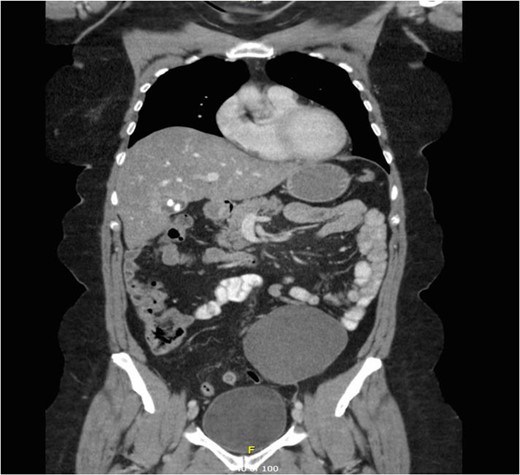

A mesenteric cyst is rare intra-abdominal pathology, with little literature to guide us on how to diagnose and manage it. We report the incident of a 57-year-old female who had an incidental finding of a sigmoid mesenteric cyst whilst undergoing an operation under the care of the Gynaecologists. A computed tomography scan and a flexible sigmoidoscopy followed to help diagnose the lesion as a cyst. A month later the 10 × 15 cm2 cyst was excised laparoscopically with no complications.

Mesenteric cysts are rare intra-abdominal lesions [1–4]. They occur in both adults and children with an incidence of 1/10 500–25 000 of adult surgical patients [5]. They are mostly found incidentally but patients with these cysts can sometimes present with non-specific complaints of abdominal pain and distension, or an abdominal mass [1]. They commonly originate in the small bowel mesentery, mesocolon (24%), retroperitoneum (14.5%) and very rarely from the sigmoid mesentery [6]. To diagnose these cysts, patients often require radiological investigations such as ultrasonography (USS), computed tomography (CT) and magnetic resonance imaging (MRI) [7]. Depending on their symptoms and location, these cysts can either be treated conservatively, or by open or laparoscopic surgical excision, and histological examination is often required to identify the origin of the cyst.